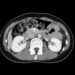

- Širdies kompiuterinė tomografija (KT).

- Širdies echoskopija (ultragarsinis tyrimas).